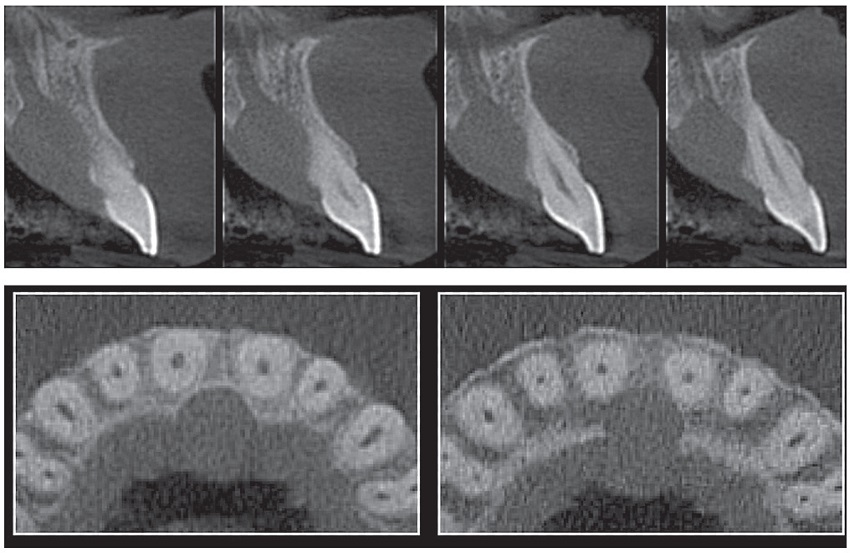

A 62-year-old male patient, Caucasian, sought the Stomatology Clinic of the Department of Dentistry of the Pontifícia Universidade Católica de Minas Gerais (PUC Minas) complaining of swelling in the anterior region of the palate. He reported realizing the condition 40 days before, which was continuously growing and painful to touch and when chewing. The anamnesis did not reveal systemic alterations. At extraoral examination, no alterations were observed. The intraoral examination showed a soft texture swelling, slightly purplish in color, with increased in translucency, suggestive of fluid content, covered by an intact mucosa, located on the anterior hard palate in the midline, close to the incisive papilla, measuring approximately 1.5 cm in diameter (Figure 1). Periapical and occlusal maxillary radiographs showed a well-defined unilocular radiolucent area in the incisive foramen region (Figure 2). Cone Beam computed tomography (CT) examination was requested to better evaluate the limits of the lesion, which showed a well-defined hypodense area, in continuity with the incisor canal, measuring 15 × 13 mm, in transversal and axial sections (Figure 3). Pulp vitality tests were performed on upper incisor teeth with a positive result for all of them. Based on the clinical and imaging characteristics, the diagnostic hypothesis of nasopalatine duct cyst was established, and the proposed treatment was surgical removal of the lesion. Under local anesthesia, aspiration of the lesion fluid was performed, which revealed the presence of translucent fluid. Subsequently, an intrasulcular incision and detachment of the palatal mucosa were performed in the region between the maxillary right and left first premolars (Figure 4). After exposure of the lesion, we performed dissection between the cystic capsule and the mucosa, which were adhered, followed by cyst enucleation and cleaning the surgical cavity (Figure 5). The mucoperiosteal flap was then repositioned and sutured.